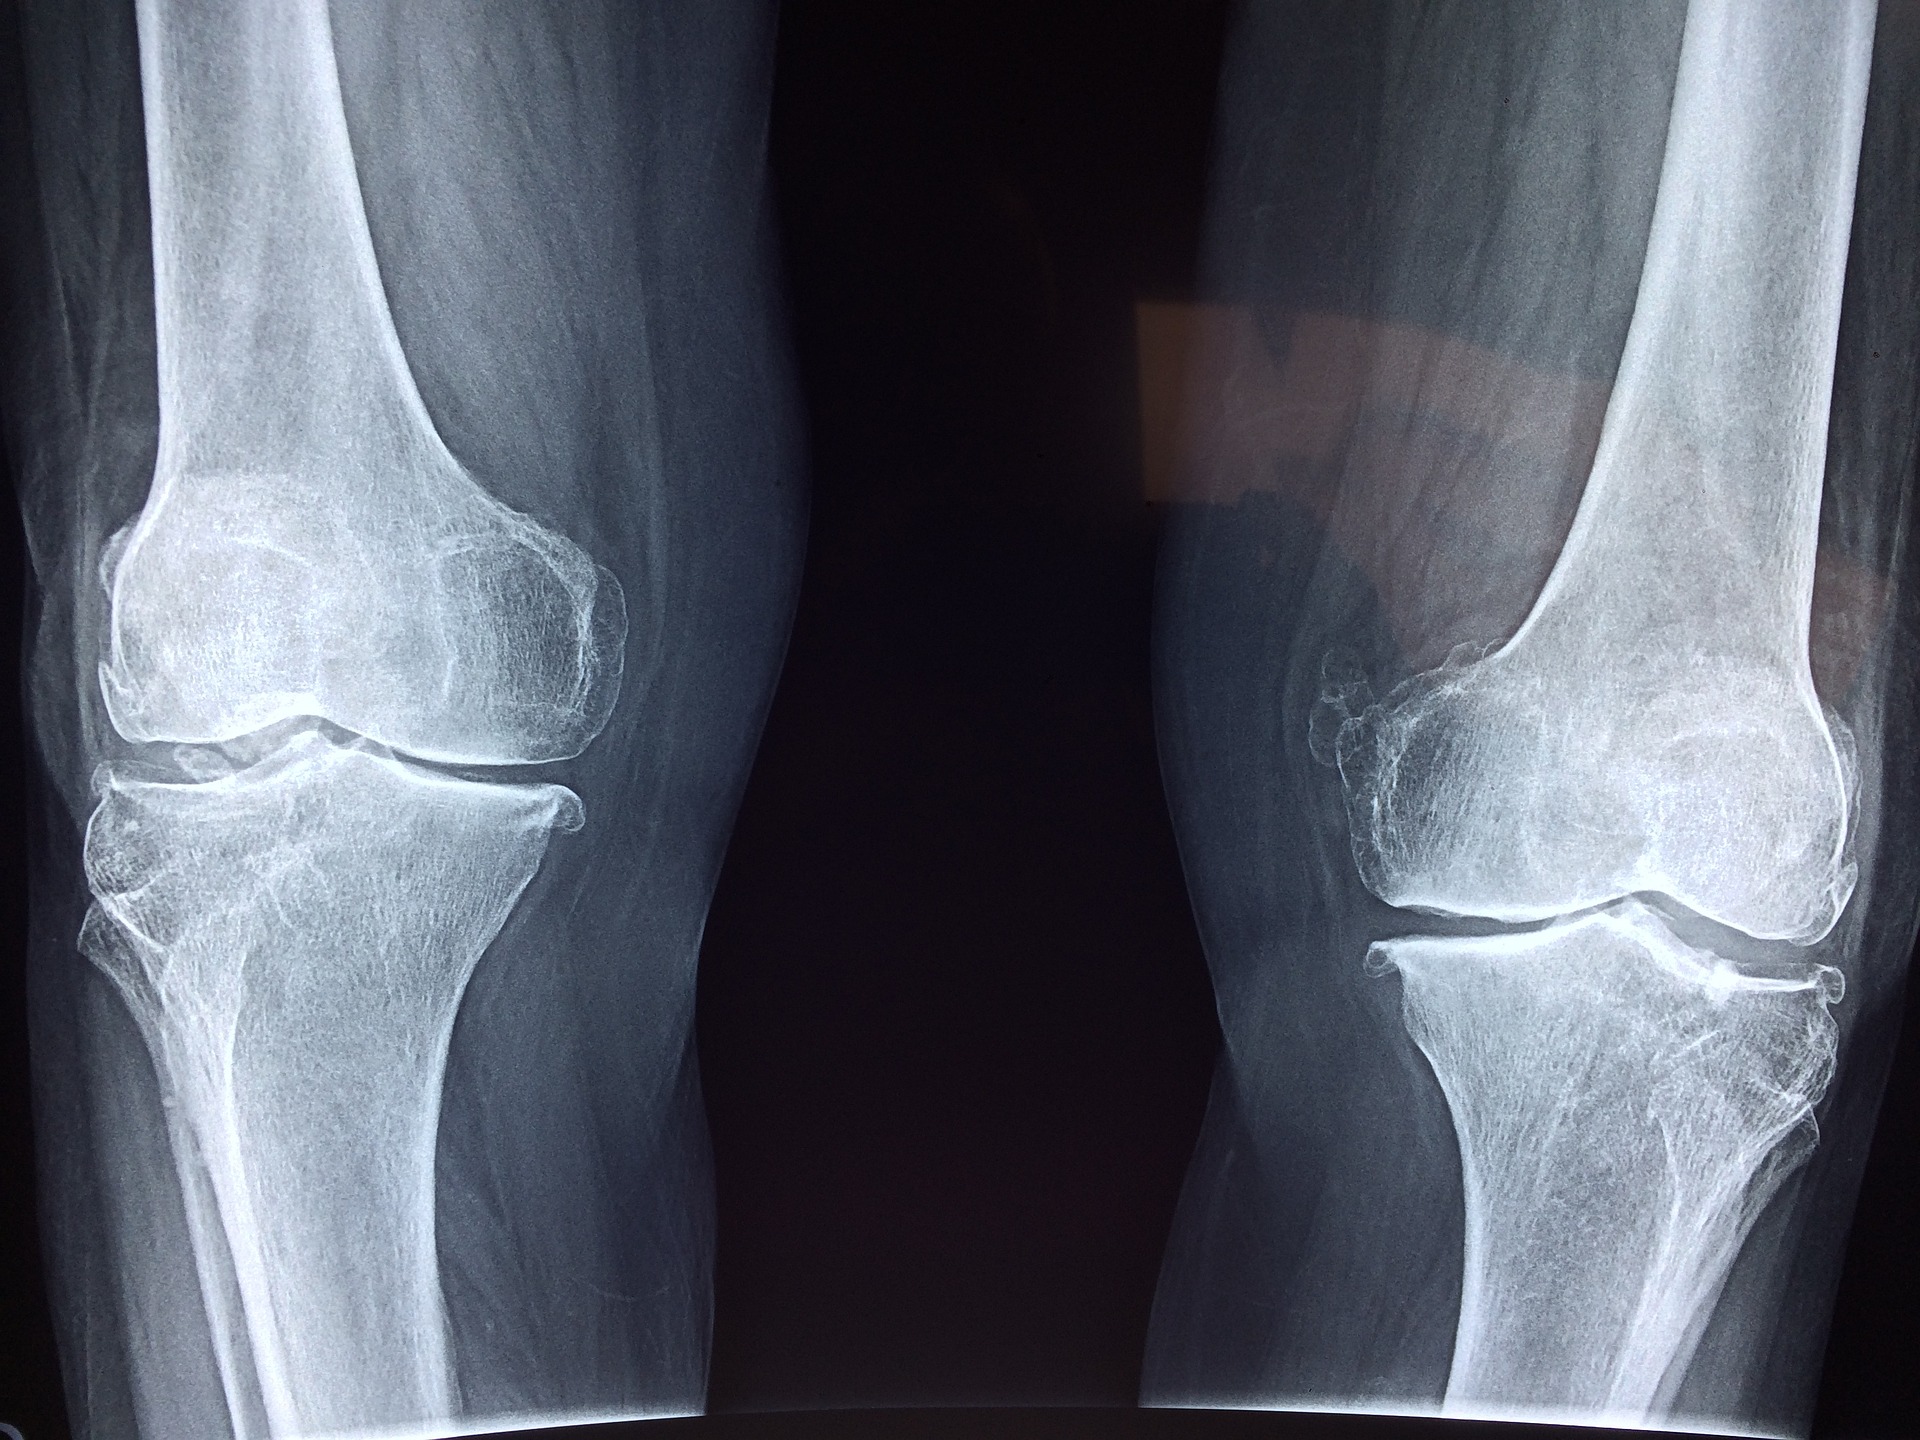

1. 무릎 부상

무릎 부상은 무릎뼈가 넙다리 아래 끝부분에 반복적으로 부딪혀 통증이 생기는 것을 말합니다. 마취 후 삽입하는 작은 관찰 장치인 관절경으로 보면 무릎뼈가 비정상적으로 보일 수 있습니다. 그러나 정상적으로 보이는 경우에도 여전히 상당한 통증이 있을 수 있습니다. 이 문제는 남성보다 여성한테서 더 흔한 경향이 있습니다. 원인은 무릎관절과 네갈래근의 다소 어긋난 배치나 다리를 움직이는 방식의 가벼운 비정상성인데 이는 훈련만으로 완화될 수 있습니다. 훈련을 마친 후 또는 오랫동안 앉아 있을 때 무릎뼈 뒤에 통증이 느껴지고 삐걱거리는 소리가 날 수 있습니다. 계단을 내려가는 것이 고통스러우며 약간의 부기도 확인할 수 있습니다.